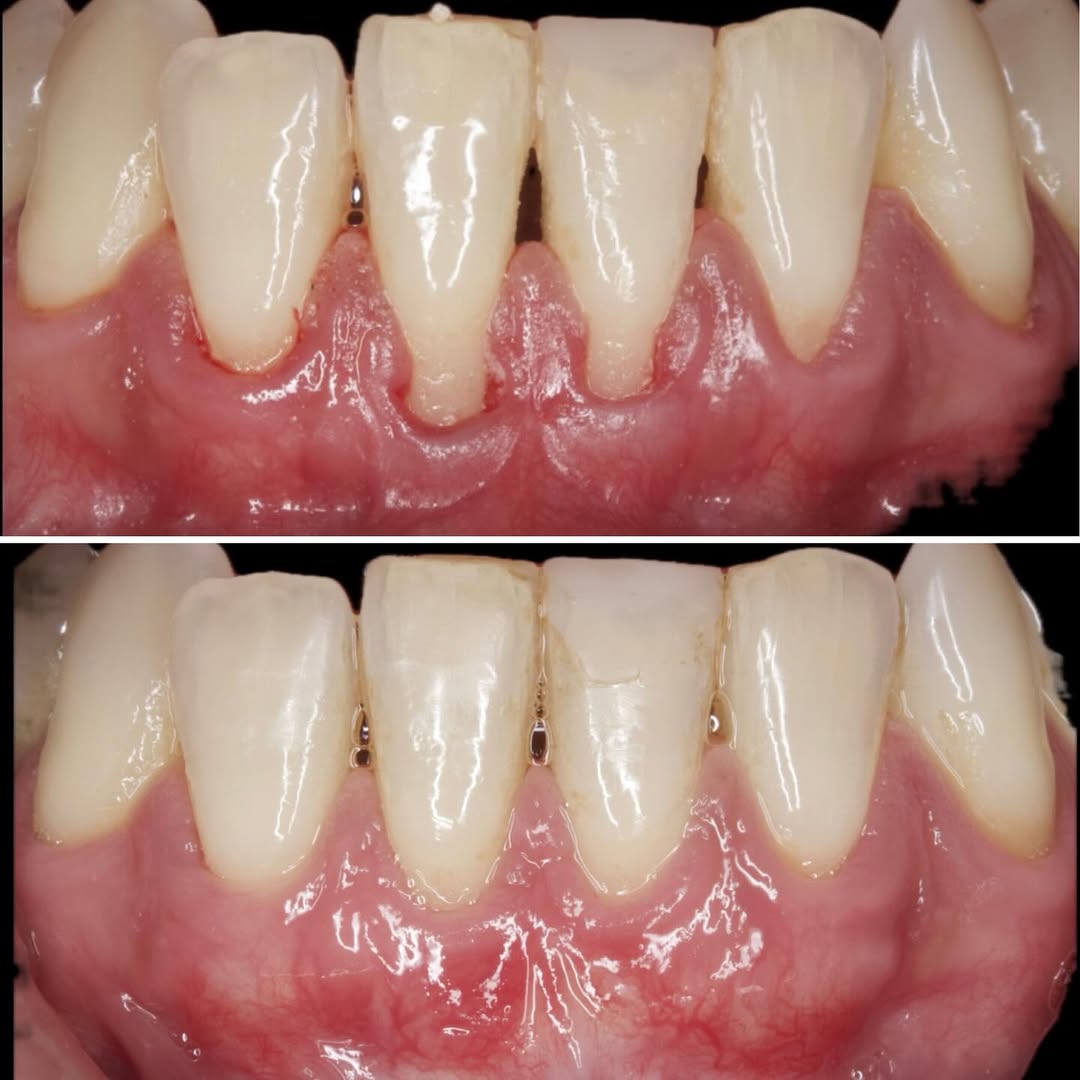

Durante una mañana, asistirás a una Cirugía Mucogingival de recubrimiento radicular de recesiones múltiples en IV y V sextante (36 a 43).

Gracias al uso del microscopio y a la proyección en tiempo real en pantalla, verás exactamente lo mismo que veo yo durante la cirugía, sin tener que estar

¿Te sientes seguro manejando recesiones múltiples o biotipos finos? Este curso está diseñado para transformar tu destreza quirúrgica en el manejo de tejidos blandos.

• Diagnóstico de Precisión: Clasificación de las recesiones y toma de decisiones basada en la

Aprende la planificación y técnica de la cirugía Mucogingival para el recubrimiento de recesiones y aumento de banda queratinizada en el sector anteroinferior

Formación teórico-práctica completa sobre las técnicas más avanzadas en cirugía mucogingival. Durante dos días intensivos, los participantes aprenderán desde la evidencia científica y la anatomía de las zonas donantes hasta la ejecución de injertos, cubrimiento radicular y aumento de